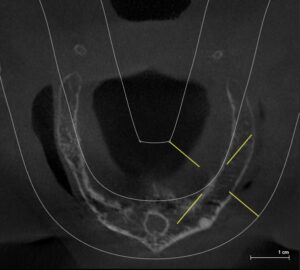

파노라마 엑스레이에서 보면 뼈가 충분해 보여서 쉽게 치료가 될 것으로 생각했지만 CT를 확인한 바 골의 폭경이 아주 좁아서 임플란트 식립에 어려움이 예상되었습니다.

CT로 보면 골질이 안좋고 골폭이 좁아

그런데 CT상으로 관찰한 바로 뼈가 있기는 한데 굉장히 무른 상태이고, 폭이 매우 좁아져 있었습니다. 치아를 뽑고 틀니를 오래 사용하신 분들 중 이렇게 뼈가 많이 약해져 있는 경우가 많습니다.

골폭이 좁은 경우에는 뼈를 조심스럽게 쪼개어 임플란트를 고정시키게 됩니다. 그래서 보다 섬세한 수술 테크닉이 필요하게 됩니다.